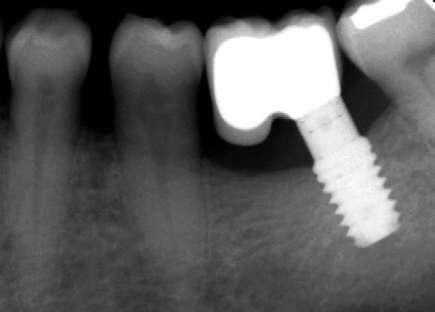

Figuras 3-6. Imágenes de un caso de prótesis atornillada en molar unitario inferior. Vemos el estado de los tejidos blandos gingivales tras la segunda fase y colocación del transepitelial unitario y la radiografía. En las imágenes inferiores (5 y 6) observamos el caso a los 4 años y 10 años de seguimiento, con estabilidad completa de los tejidos óseos peri-implantarios.

Figuras 7-10. En las dos imágenes superiores (7 y 8) observamos la realización de la prótesis cementada mediante un bioplilar fresado a la altura gingival con la radiografía antes del cementado de la corona. En las imágenes inferiores (9 y 10) vemos la prótesis a los 7 años de seguimiento y a los 9 años transformada en una prótesis atornillada al perderse la pieza anterior al implante y realizarse un puente con el nuevo implante. En este caso, el nivel óseo permanece estable con el paso del tiempo.